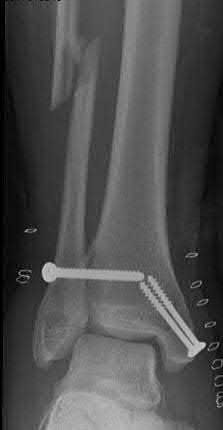

A 25-year-old male sustains an ankle fracture dislocation and undergoes open reduction and internal fixation. He returns to clinic five months following surgery complaining of continued ankle pain and instability with weight bearing. His immediate post-operative AP radiograph is seen in Figure A. Which of the following could have prevented this patient from developing persistent pain?

The patient presents with continued ankle pain and instability following open reduction and internal fixation. The radiograph in figure A demonstrates inadequate restoration of fibular length, likely leading to continued tibiotalar instability.

Illustration A demonstrates fibular malreduction with dislocation of the fibula anterior to the tibial incisura. Illustration B shows a comminuted fibula fracture along with a measurement of length from an intact fibula. The arc from the lateral process of the talus to the peroneal groove of the distal fibula is known as the "dime" sign and should remain unbroken if fibular length has been restored. Illustration C demonstrates the use of a push-pull screw and lamina spreader to regain length intraoperatively for a comminuted fibula fracture.

Chu and Weiner review management of malunions of the distal fibula. The authors state that restoration of fibular length, alignment and rotation leads to reduction of the talus, provides a buttress to talar motion in the setting of an incompetent deltoid, and allows the syndesmotic ligaments to heal at the appropriate tension.

Wikeroy et al conducted a study of patients from a prior prospective, randomized control trial comparing different methods of syndesmotic fixation. There was no significant difference in outcomes between tricortical or quadricortical 3.5mm screw fixation, however worse outcomes were seen with associated posterior malleolar fractures, obesity, a difference in sydesmotic width of 1.5mm or greater, and a CT confirmed tibio-fibular synostosis.

Sinha et al present a simple technique for fibular lengthening in the setting of distal fibula malunion. They found high union rates and improved AOFAS scores at short-term follow up with their technique.